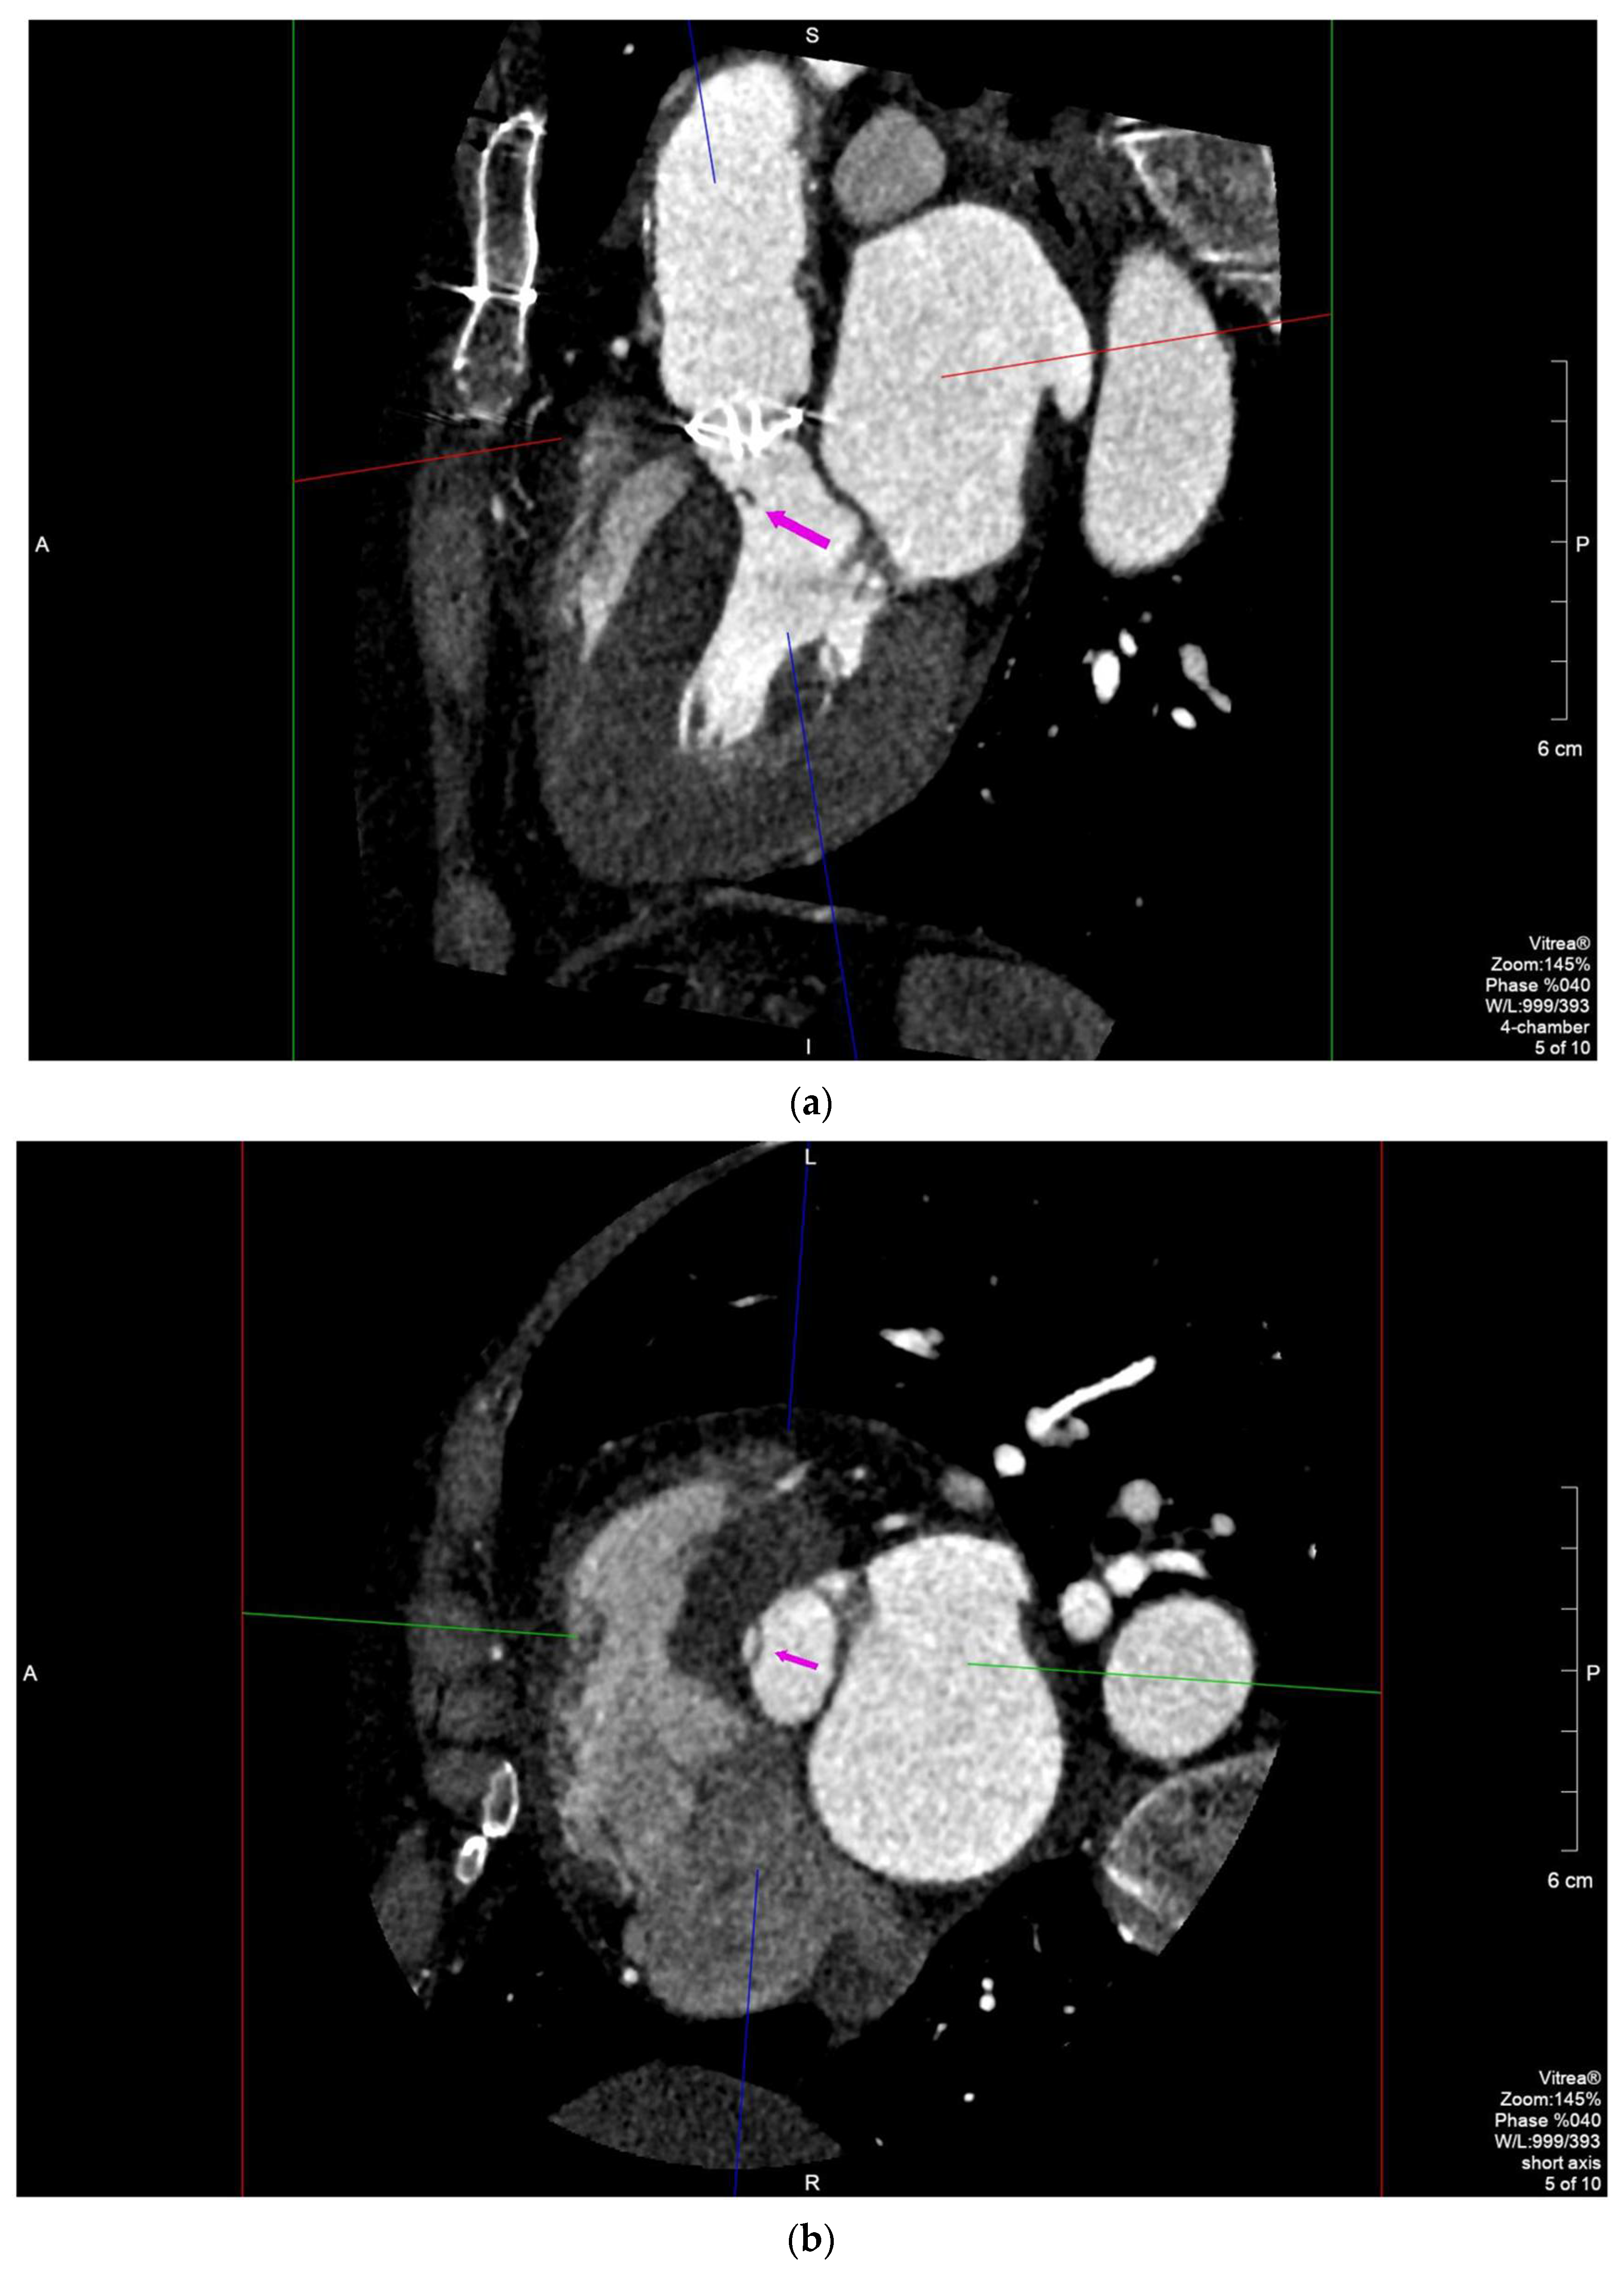

2.2. Case 2